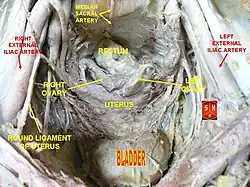

The bladder is located below the peritoneal cavity near the pelvic floor and behind the pubic symphysis. In males, it lies in front of the rectum, separated by the rectovesical pouch, and is supported by fibres of the levator ani and of the prostate gland. In females, it lies in front of the uterus, separated by the vesicouterine pouch, and is supported by the elevator ani and the upper part of the vagina.[10]